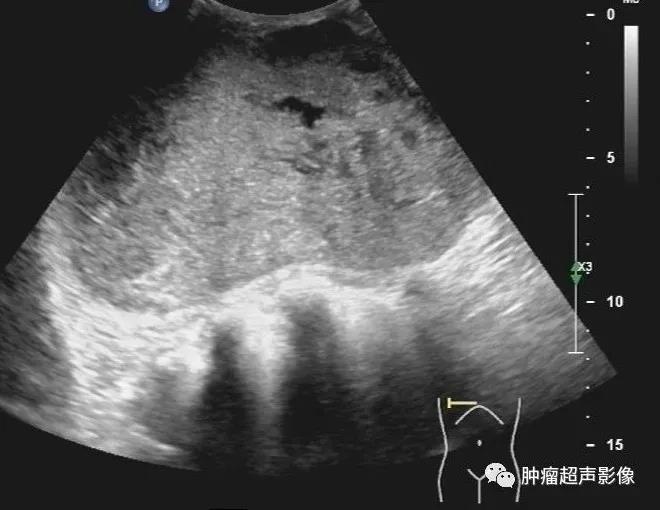

交界性叶状肿瘤: 女,边界清,肿块巨大,皮肤变薄,假包膜,裂隙状无回声及条索状高回声,血流稍丰富,超声造影见明显无增强区,表现为典型叶状肿瘤。